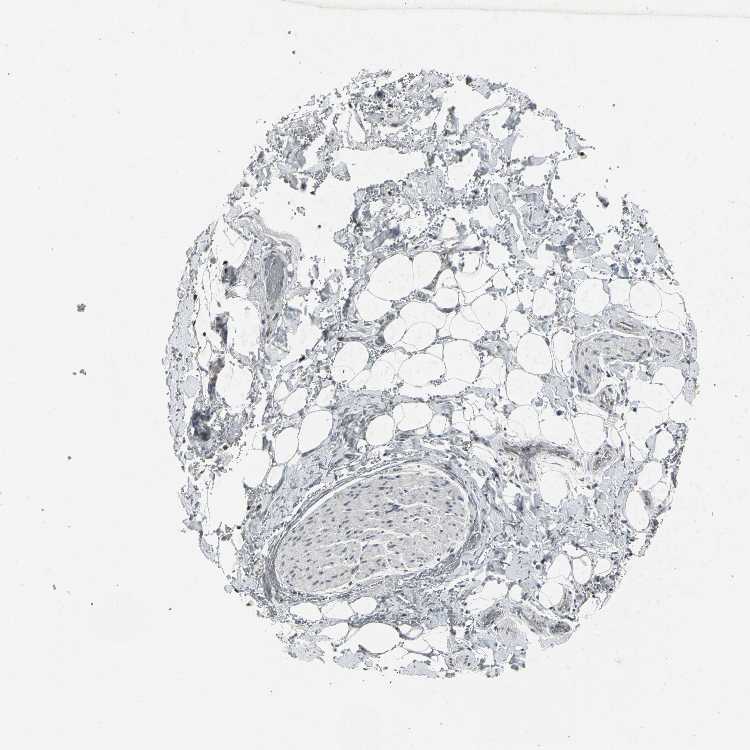

TISSUE PRIMARY DATA SOFT TISSUE Show tissue menu

SOFT TISSUE - Expression summary

SOFT TISSUE 1 - Antibody stainingi

Antibody staining in the annotated cell types in the current human tissue is reported as not detected, low, medium, or high, based on conventional immunohistochemistry profiling in selected tissues. This score is based on the combination of the staining intensity and fraction of stained cells.

Each image is clickable and will lead to virtual microscopy that enables deeper exploration of all samples and also displays staining intensity scores, fraction scores and subcellular localization as well as patient and tissue information for each sample.

Antibody HPA066235Antibody CAB006863

Chondrocytes Not detectedLow

Fibroblasts Not detectedNot detected

Peripheral nerve -Not detected

SOFT TISSUE 2 - Antibody stainingi

Peripheral nerve Not detected-